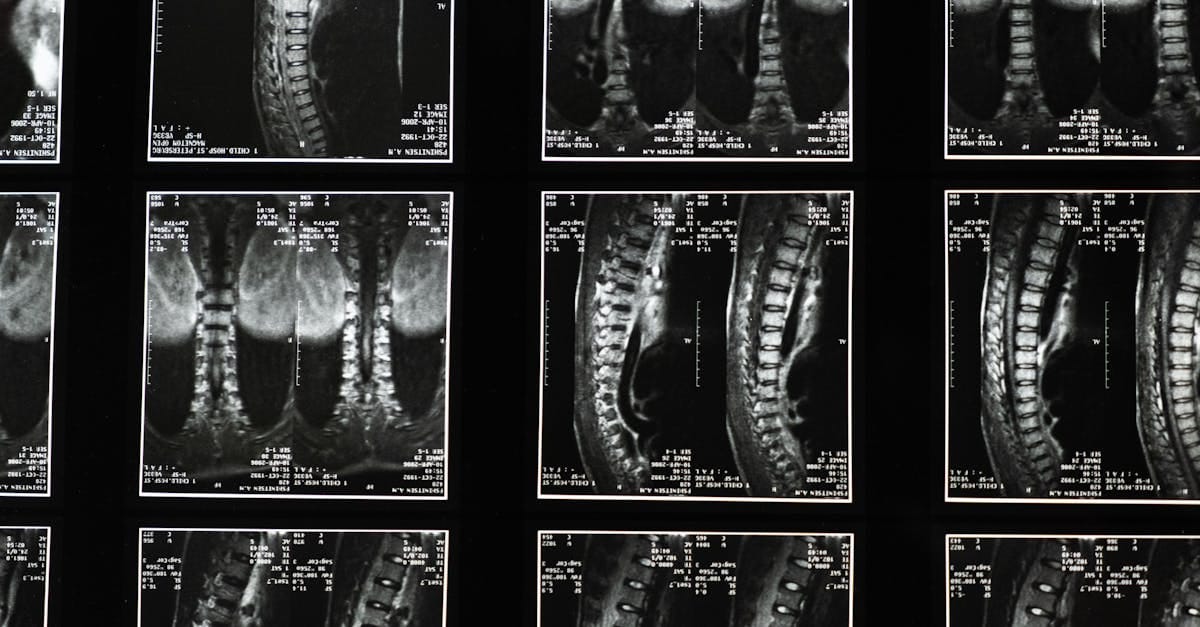

Quels examens permettent de déterminer l’éligibilité à la décompression?

Une consultation clinique et des examens d’imagerie comme l’IRM sont nécessaires pour déterminer l’éligibilité.